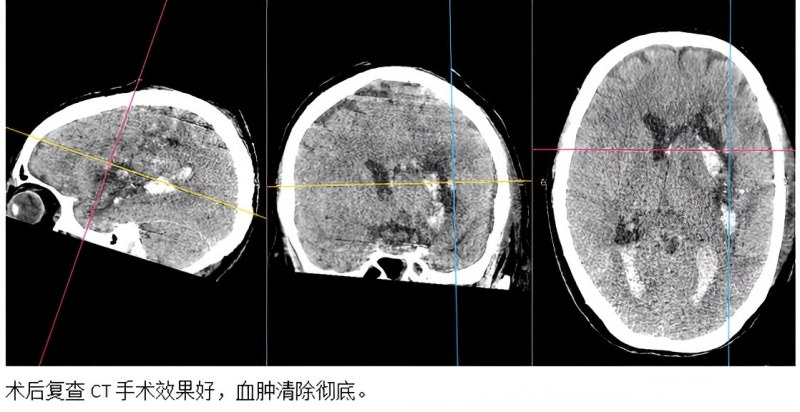

传统开颅手术风险高、花费多,且因该患者血肿巨大、形态不规则,常规的单一通道穿刺血肿引流无法充分清除颅内血肿。结合患者病情及颅内出血特点,神经外科一病区徐阳医生迅速做出判断,为其制定了个性化多微创途径的手术方案。经过神经外科一病区与重症医学科医护人员高度协同,短时间内完成术前准备,在CT精准定位引导下联合应用“硬通道与软通道血肿穿刺术”完成手术治疗。颅内大量血肿短时间内被彻底清除,取得了较好的手术效果。